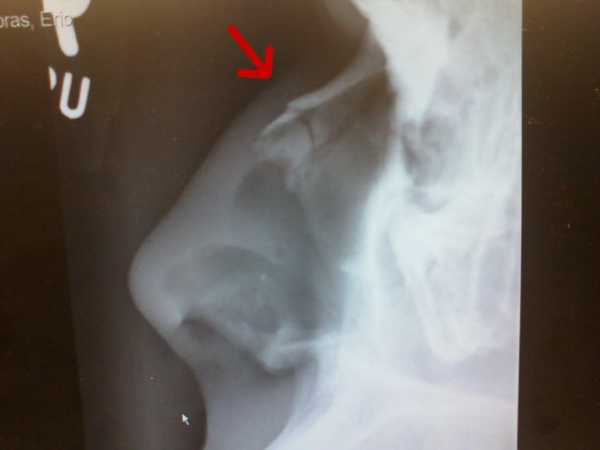

С данной травмой обращаются к врачу — отоларингологу. Врач осмотрит пациента, оценит степень травмы, соберет анамнез. При пальпации носовой области определит болезненный участок, наличие воздуха, крепитацию фрагментов кости и подвижность наружного носа. Также специалист выявит вид деформации носовой пирамиды и степень отека мягких тканей. Очень важно обратить внимание на наличие у пострадавшего кровотечения и головной боли, потери сознания, рвоты или тошноты. Обязательно проводят инструментальные исследования — рентген и риноскопию.

Рентгенографическое исследование поможет определить вид травмы (открытый, закрытый, со смещение или без) и локализацию повреждения (иногда это можно определит путем пальпации). Риноскопия выявляет степень отека слизистой оболочки, вероятное искривление перегородки, место разрыва слизистой и первоисточник носовой геморрагии. Важно определить наличие сопутствующих недугов и носовых повреждений в прошлом.

Рентгенографическое исследование черепа. Снимки, полученные в ходе обследования, позволяют врачу увидеть места перелома и количество, а также смещение отломков. Помимо травмы органа дыхания, с помощью рентгенографического исследования выявляются возможные повреждения черепных костей.

Рентген носа позволяет не только определить локализацию отломков и состояние костей травмированного органа, но и сопутствующие повреждения черепа. На рентгеновском снимке четко видны разрывы костной ткани и все линии перелома. Рентгенография осуществляется в двух проекциях для более полного поминания травмы.